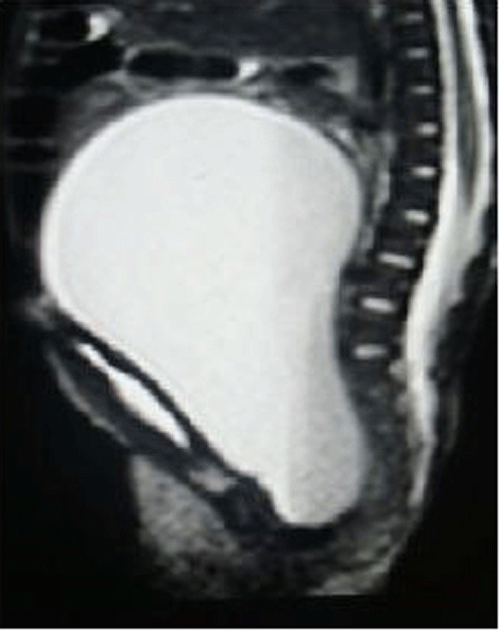

USG suggested a large hydrometrocolpos. MRI scan (Fig. 4), showed large hydrometrocolpos with atretic lower vagina and associated bilateral hydronephrosis. Genitogram revealed no communication between bladder and vagina. Echocardiography suggested a VSD with a PDA. A cutaneous vaginostomy was done and post-operative recovery was uneventful. At 4 month follow up, child is thriving well and is awaiting definitive vaginal reconstruction.

Figure 4: MRI of hydrometrocolpos with vaginal atresia. |